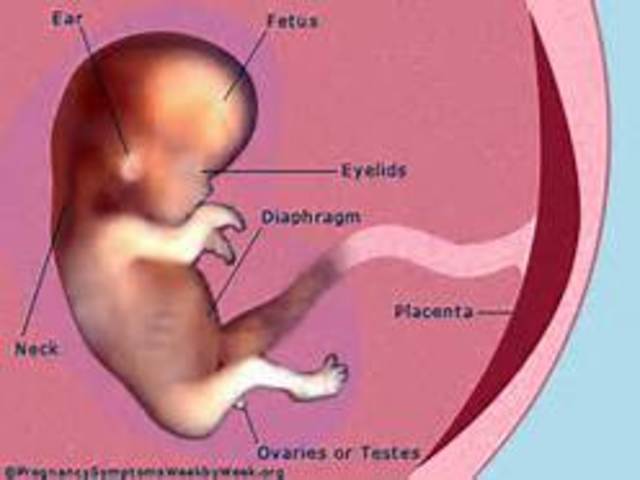

Week 10

In week ten, the baby becomes a fetus and all of its organs, nerves, and muscles begin to function within its body. During this week of development the fetus is about the size of a strawberry.,

• Week 11

Week 11

By week eleven, the baby has begun developing ears, toes, an upper lip, and twenty teeth. Also during this week the genitals of the baby have begun to develop.